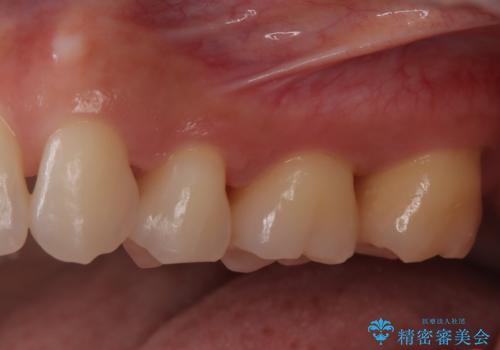

- 定期的にクリーニング(保険適応)に通って頂いている患者さんです。歯周ポケットが4ミリあったため歯茎を開いて歯石を除去するためにオープンフラップ術を行うことにしました。

歯周ポケットがそれほど深くない患者さんでしたが、いざ歯茎を開いてみるとそこにはたくさんの歯石がありました。もし歯周ポケットが4ミリだからと言って放置していれば数年後には、沢山の骨が無くなっていたことが予期出来ます。現段階で歯茎の下にある歯石を除去することにより骨が無くなることを予防する事が出来ました。